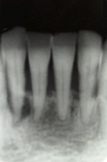

歯と歯ぐきの隙間を歯周ポケットといいます。歯石は歯周ポケット内にも沈着し、細菌が溜まりやすい環境を作ります。 細菌が溜まる事により骨を溶かし、歯周病を進行させます。歯周ポケット内の歯石は血液と細菌が混ざり黒い色をしています。

そして、とても硬く沈着している為簡単には取れないので、手作業や機械を使用し時間をかけて除去します。

歯周ポケット内の歯石を放置していると、歯ぐきの腫れや出血が引かず、気付かないうちに歯を支えている歯槽骨が溶け、歯がグラグラ動きだします。

そこまで重度の歯周病になると、歯を保存する事が難しくなり、抜歯となる可能性がでてきます。そうならない為に、歯周ポケット内の歯石除去が必要となります。

歯と歯ぐきの間にプラークがたまって歯ぐきが腫れ、出血しやすくなっています。歯を支える骨にはまだあまり影響がありません

歯周ポケットが形成され、歯石が深部まで付着し、歯を支える骨を半分くらい失っています